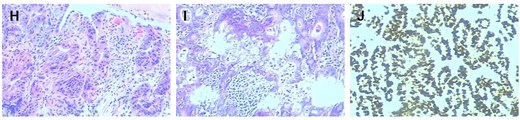

The diagnosis of gastric cancer was confirmed, and the possibility of a malignant pancreatic tumor could not be excluded. Surgery was performed on 20 June 2021, with the preoperative plan involving pancreaticoduodenectomy and partial gastrectomy. Intraoperative findings revealed no abdominal ascites and no abnormal nodules in the peritoneum, liver, colon, or small intestine, and no tumor invasion in the stomach. A 6 × 5 cm mass was identified in the lymph node station of group 8, characterized by a hard texture, limited mobility, and close association with surrounding blood vessels, while no obvious thickening was seen in the antrum (Fig. 2). Scattered lymph nodes were found around the stomach. The tumor was located at the upper origin of the pancreas and could be separated from the pancreatic tissue. Based on intraoperative findings, early gastric cancer with lymph node metastasis was suspected. Consequently, radical distal gastrectomy and tumor resection were performed. Postoperative pathology showed that group 8 lymph nodes measured 7.5 × 5.3 × 4.0 cm and appeared gray and brittle. The partial gastrectomy specimen measured 13.0 × 4.5 × 3.5 cm. Gastric intramucosal carcinoma (well-differentiated, Fig. 3H) was identified, with no evidence of vascular tumor emboli or nerve invasion. Surgical margins and the omentum were free of cancer. Two metastatic lymph nodes were found in Group 8, while no metastasis was detected in the remaining lymph nodes. Immunohistochemical analysis of the gastric mass showed C-erbB2 (2+), Ki-67 index 90%, CK7 (focal +), CK20 (−), CA125 (−), CA199 (−), Villin (+), and CDX2 (+). For group 8 lymph nodes, results were CK7 (+), CK20 (−), CA125 (−), CA199 (−), Villin (+), and CDX2 (+) (Fig. 3I and J).

Histopathological and immunohistochemical analysis (×200 magnification). (H) The preoperative gastroscopic biopsy immunohistochemistry (×200) results were highly suspicious for malignancy. (I) Immunohistochemical analysis of the resected gastric carcinoma specimen (×200) supports the diagnosis of early gastric cancer. (J) Histopathological evaluation of the resected specimen confirmed metastatic involvement of the lymph node tissue (×200).